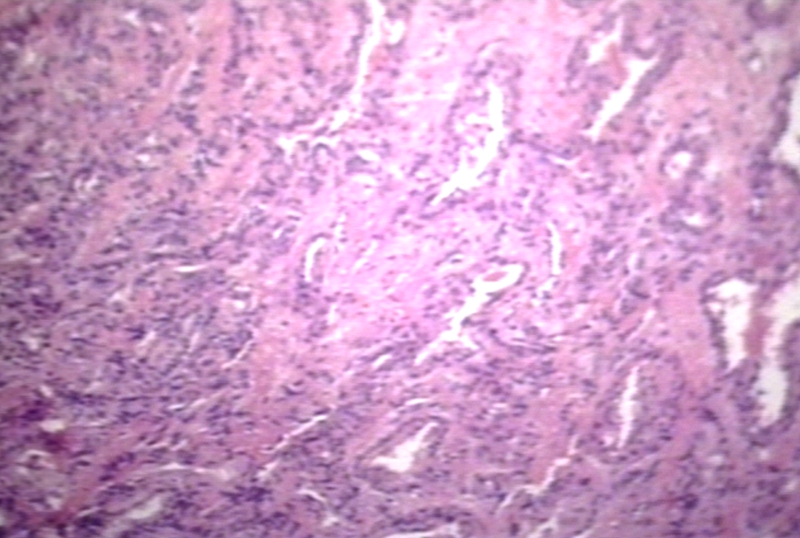

HISTOLOGY: SOFT TISSUE: ENDOTHELIOMA, HEMATOGENOUS